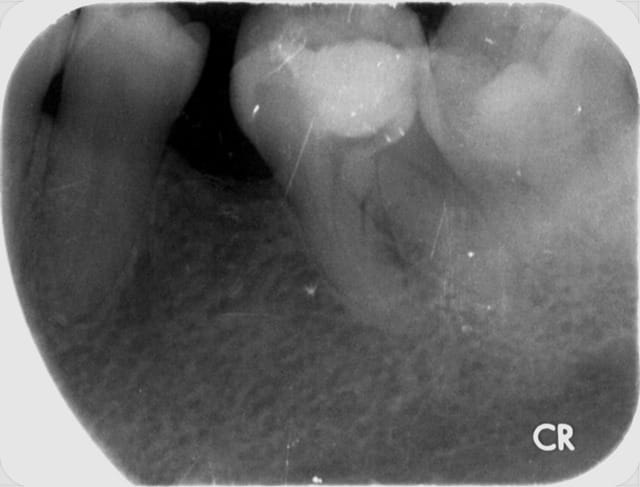

Ben alors j'ai un cas là justement : je fais quoi? Onlay ou Couronne?

Dent vivante, CVI renforcé après la taille en coiffage attente de 3 semaines avec pansement pour être sûr, RAS dent toujours vivante quand je l'ai revu aujourd'hui.

Aujourd'hui : retouche du CVI puis (première photo au stade du mordançage) compo pour le core build-up, pansement.

Les photos sont pas top mais pour le moment je fais avec ce que j'avais sous la main...

Qu'est-ce que je fais pour la suite du coup? Onlay ou Couronne?

PS. On ne voit pas bien la différence à la radio avant-après... Désolé.

Perso je penche pour la couronne...